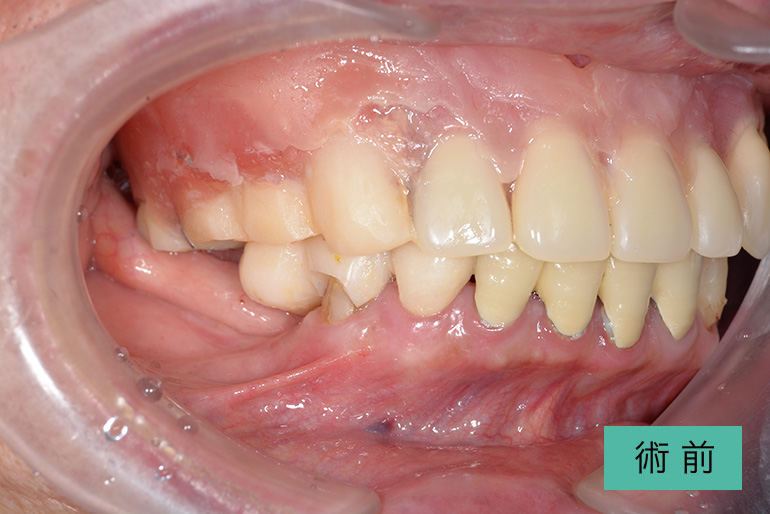

| 治療内容 | 上顎前歯右上3番から左上3番のセラミック冠 |

| 治療期間・回数 | 約1ヶ月、3回 |

| 費用(税込) | ¥990,000(165,000/1本)(補綴費用) ※自由診療 |

| リスク・副作用 | 疼痛、補綴物の脱落、咬合違和感、破折 |